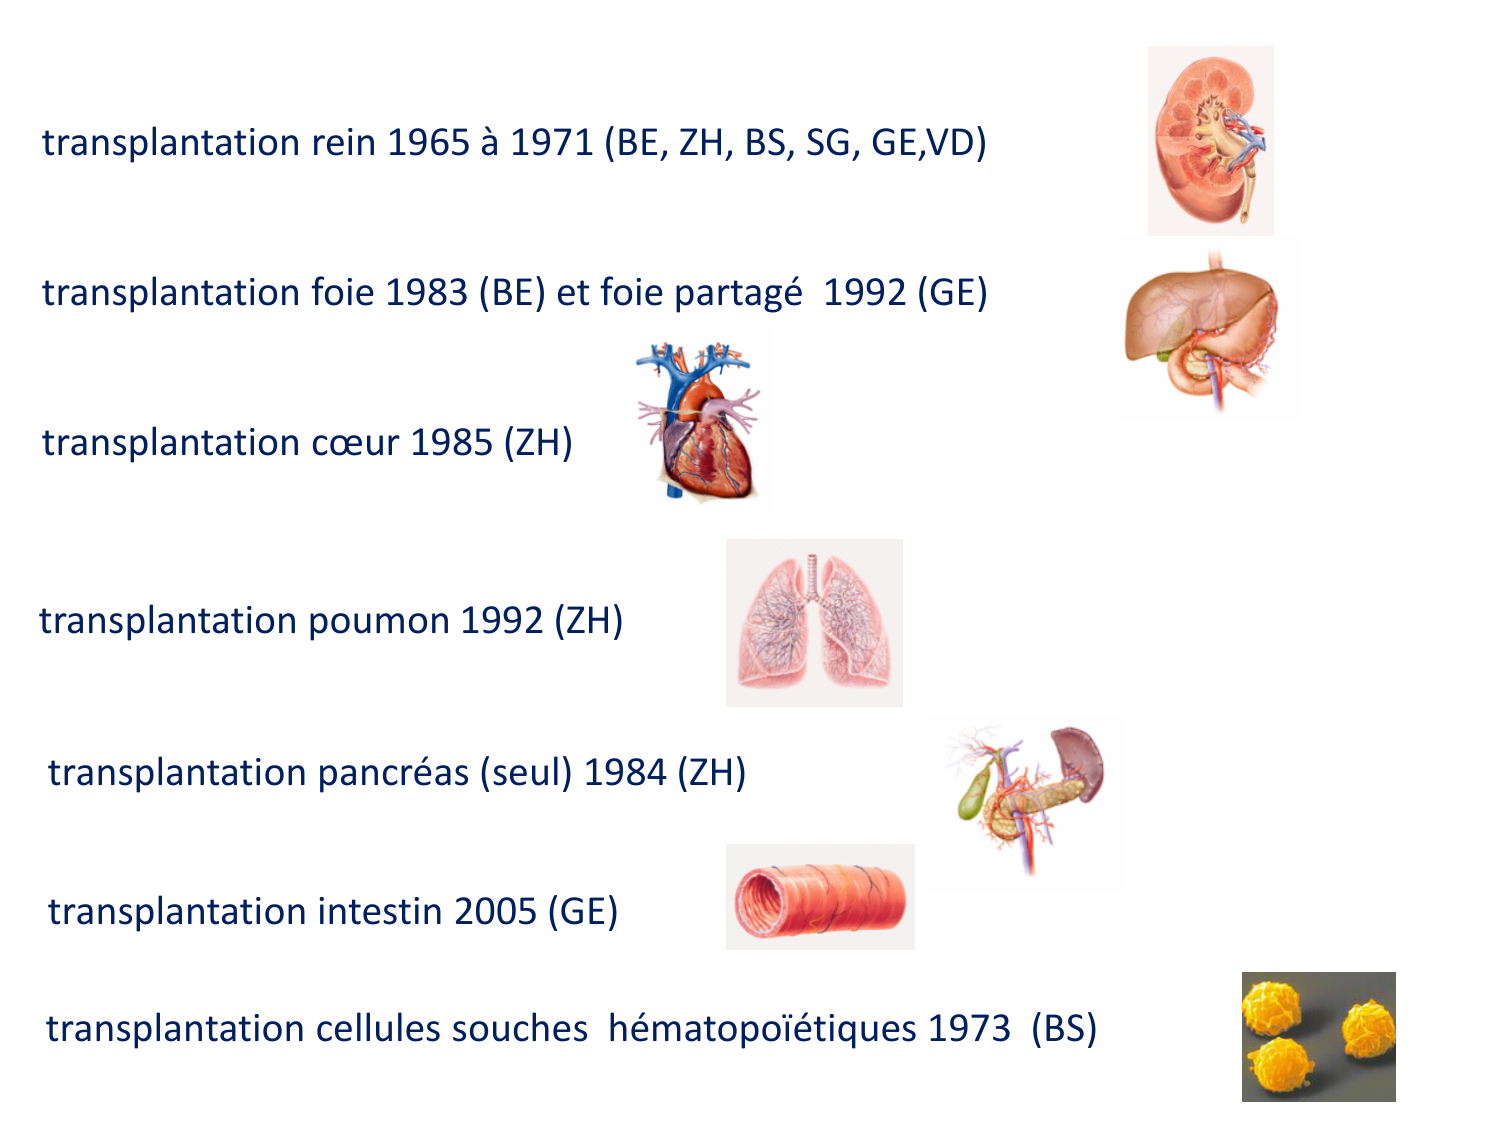

SMB4 Systèmes physiologiques 2 Immunologie, inflammation, transplantation · 61 pages · 8 sections